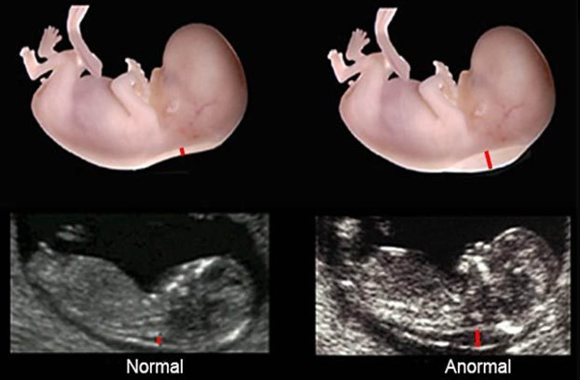

Es un examen que mide el engrosamiento del pliegue de la nuca. Esta es un área de tejido en la parte posterior del cuello de un feto.

Los valores de referencia de la translucencia nucal pueden ser: Normal: inferior a 2,5 mm; Alterada: igual o superior a 2,5 mm.

• Para medir el pliegue de la nuca el proveedor de atención médica realiza el ultrasonido abdominal (no vaginal). Todos los fetos tienen algo de líquido en la parte posterior de su cuello. En un bebé con síndrome de Down u otros trastornos genéticos, hay más líquido de lo normal.